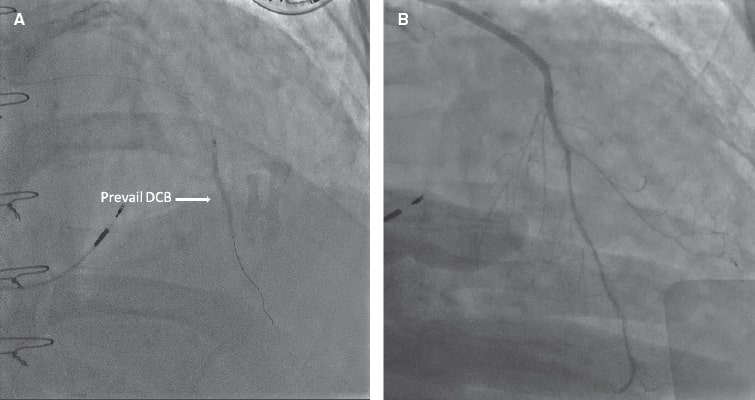

Afterwards, a Thrombuster II (Kaneka Corp., Japan) aspiration device was advanced into the mid LIMA. Contrast injection revealed an occlusion at the LIMA–LAD anastomosis (figure 1F, arrow). Although thrombectomy restored flow, severe stenosis persisted at the anastomosis site. Balloon angioplasty was performed, followed by the deployment of a 2.0 mm × 30 mm Prevail (Medtronic, United States) drug-coated balloon (DCB) across the graft and native LAD (figure 2A, arrow). Final angiography demonstrated excellent runoff (figure 2B; video 2), ST-segment resolution, and hemodynamic improvement.

Figure 2.